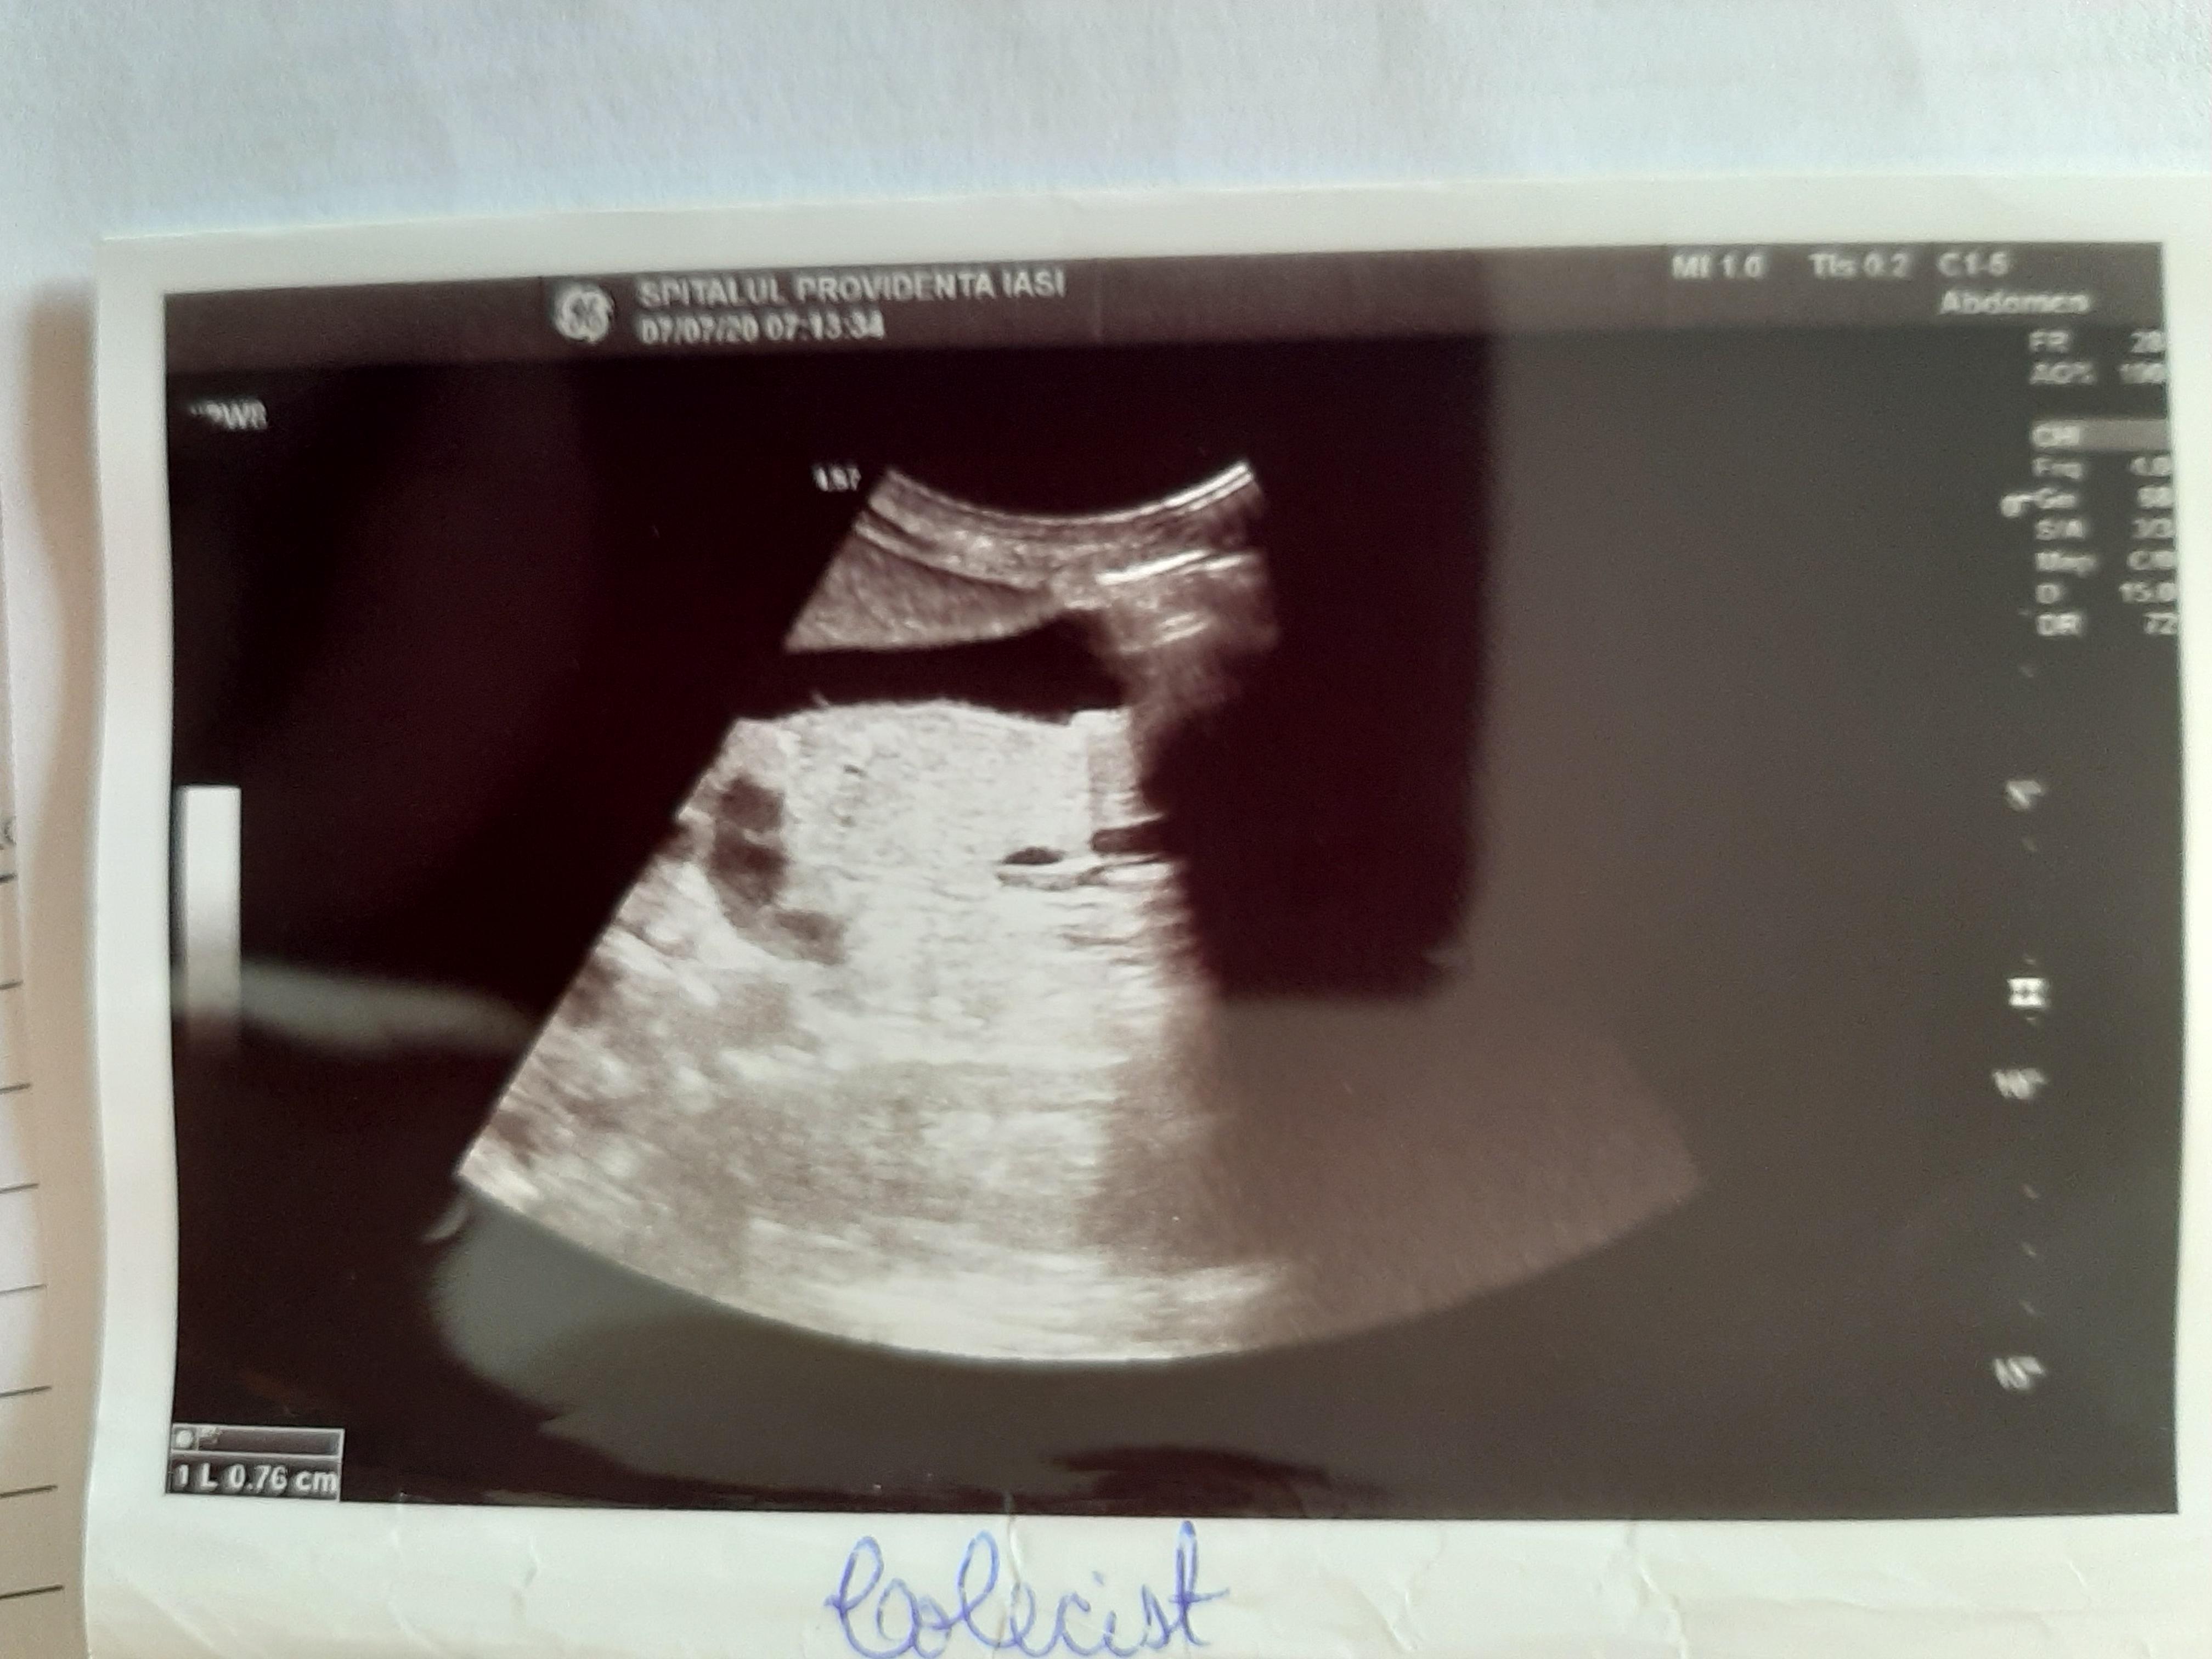

Diagnosticul medicilor a fost: sindrom hipoanabolic, litiază biliară veziculară, boală de reflux gastroesofagian, antecedente de colită repetată cu Clostridium Difficile.